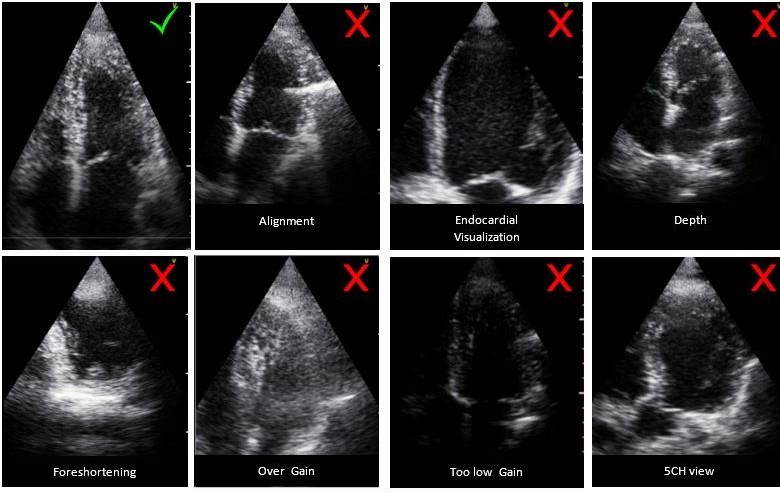

To obtain a proper EF measurement, follow the below guidelines

- Length of at least 1.5 beats.

- Septal alignment - The interventricular septum should be parallel to the image plane and endocardial border.

- Endocardial visualization – At least 2/3 of the endocardium should be visualized.

- Depth - Proportion of left ventricle (LV) to left atrium (LA) will be 2/3-1/3 (Optimum depth will be 14-18 cm).

- Avoid foreshortening of the apex.

LVivo EF measurement guideline